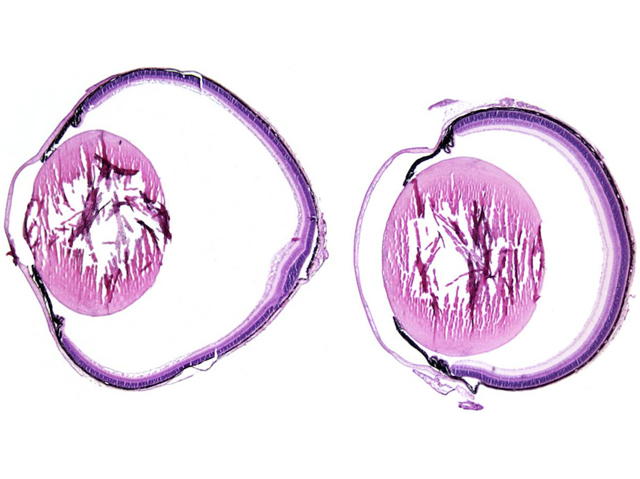

Often held up as one of the most extraordinary products of evolution, the eye is a remarkable piece of optical machinery. Any change to its structure is likely to interfere with vision, as exemplified by patients with buphthalmia, a condition in which the excessive growth of eye tissues causes dramatically enlarged eyeballs. This prevents light from focusing on the retina, leading to severe myopia, or short-sightedness. Researchers investigating the development of the mammalian eye recently identified a key gene in this process, LRP2, which codes for a receptor that intercepts growth signals in the eye, thus halting its expansion at the appropriate time. As shown by these eye sections, mice defective in LRP2 develop much larger eyes (left image) than do healthy individuals (right).This breakthrough contributes both to our understanding of the underlying cause of certain myopias, and to piecing together the development of an exquisitely complex organ.